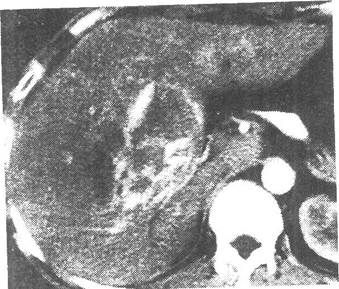

患者男性,49岁,发现乙肝十余年,反复腹痛,腹胀黄疸月余,CT图像如下,最有可能的诊断是( )。

动脉期增强 门静脉期增强

[单选题]患者男性,49岁,发现乙肝十余年,反复腹痛,腹胀黄疸月余,CT图像如下,最有可能的诊断是( )。CT平扫动脉期增强门静脉期增强A.肝肉瘤B.肝血管瘤

[单选题]患者男性,49岁,发现乙肝十余年,反复腹痛,腹胀黄疸月余,CT图像如下,最有可能的诊断是( )。CT平扫动脉期增强门静脉期增强A.肝肉瘤B.肝血管瘤

[单选题]患者男,49岁。发现乙肝十余年,反复腹痛,腹胀黄疸1个月余,CT图像如下,最有可能的诊断是A.肝血管瘤B.肝再生结节C.肝癌D.肝肉瘤E.肝腺瘤

[单选题,A2型题,A1/A2型题] 患者男性,49岁,发现乙肝十余年,反复腹痛,腹胀黄疸月余,CT图像如下,最有可能的诊断是()。A . 肝肉瘤B . 肝血管瘤C . 肝癌D . 肝再生结节E . 肝腺瘤

[单选题]患者男性,49岁,发现乙肝十余年,反复腹痛,腹胀黄疸月余,CT图像如下,最有可能的诊断是( )。A.肝肉瘤B.肝血管瘤C.肝癌D.肝再生结节E.肝腺瘤

[单选题]患者男性,49岁,发现乙肝十余年,反复腹痛,腹胀黄疸1个月余,CT图像如下,最有可能的诊断是()A.肝血管瘤B.肝再生结节C.肝癌D.肝肉瘤E.肝腺瘤

[单选题]患者男性,49岁,发现乙肝十余年,反复腹痛,腹胀黄疸1个月余,CT图像如下,最有可能的诊断是()。A . 肝血管瘤B . 肝再生结节C . 肝癌D . 肝肉瘤E . 肝腺瘤